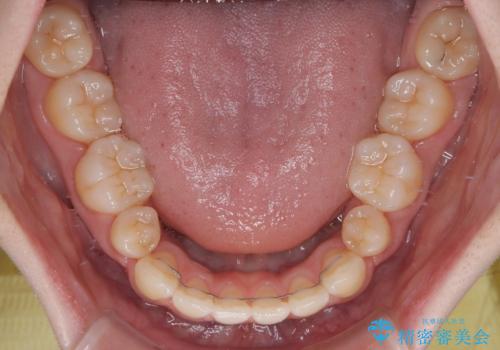

- 口元から飛び出てしまう前歯を気にして来院された患者様です。

上下前歯が嘴のように前方に突出しており、唇が閉じにくい状態であったため、上下左右の第一小臼歯4本を抜歯して、口元の突出感を改善することとしました。